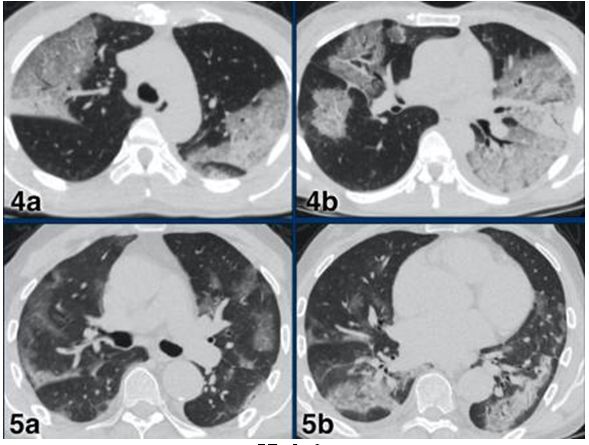

CO-RADS 5: Hình 8 & 9

Hình 8:

Trường hợp 1: Tổn thương đa ổ dạng GGO & đông đặc

Trường hợp 2: Tổn thương đa ổ dạng GGO kèm theo giãn mạch (vòng tròn) & dải băng dưới màng phổi (mũi tên)

Trường hợp 3: Tổn thương GGO & đông đặc cả 2 bên xu hướng vùng sau ngoại vi & nền phổi kèm theo giãn mạch (vòng tròn)

Hình 9:

Trường hợp 4 a & b: Tổn thương đa ổ dạng GGO & đông đặc cả 2 bên phổi

Trường hợp 5a & b: Tổn thương đa ổ dạng GGO & đông đặc xu hướng vùng ngoại vi vùng sau.